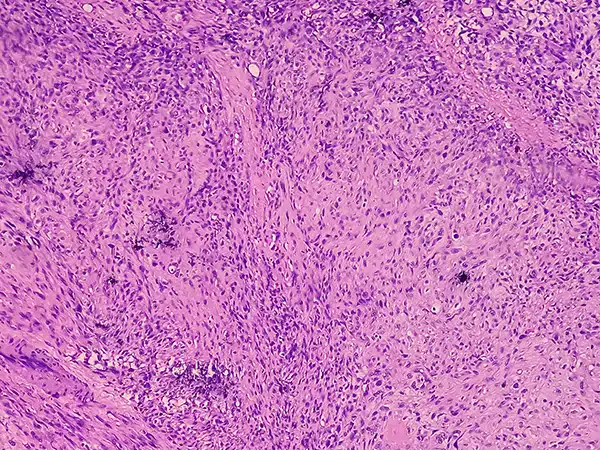

Wen-Yang Lin’s work at Stanford University focuses on creating a pharmacogenomic map of lung cancer.